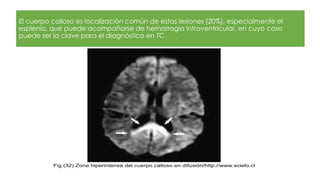

El cuerpo calloso es localización común de estas lesiones (20%), especialmente el

esplenio, que puede acompañarse de hemorragia intraventricular, en cuyo caso

puede ser la clave para el diagnóstico en TC.

Fig (32).Zona hiperintensa del cuerpo calloso en difusión/http://www.scielo.cl